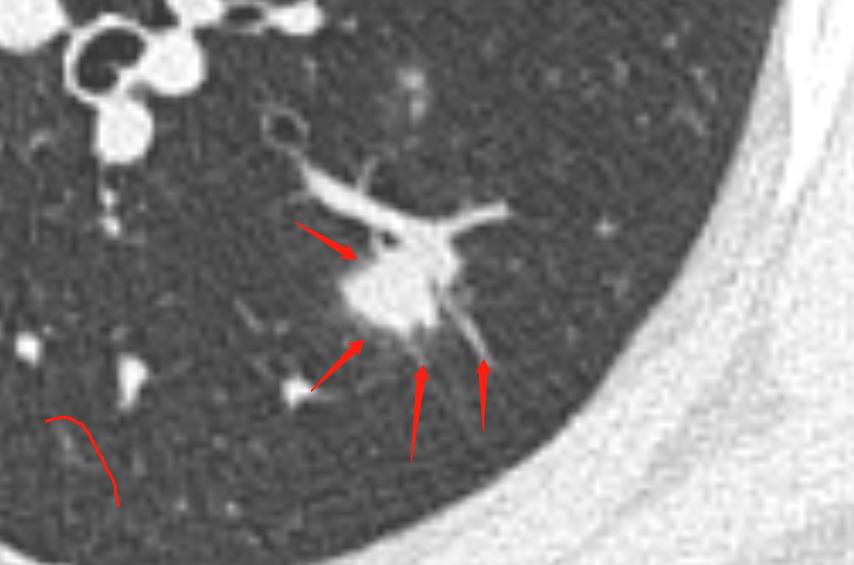

通过以上图片,病灶确实为实性结节,大小约1.0cm×0.9cm×1.0cm,呈浅分叶,周边可见毛刺,可见小血管穿入,但是影像学还是有一些不符合恶性肿瘤的特点:

1.病灶周边有一些渗出性改变。

2.相对1cm大小的肺结节来说,周边的毛刺有点长。

3.病灶及周边有扩张的支气管影。

4.病灶周边血管明显有贴边征象。